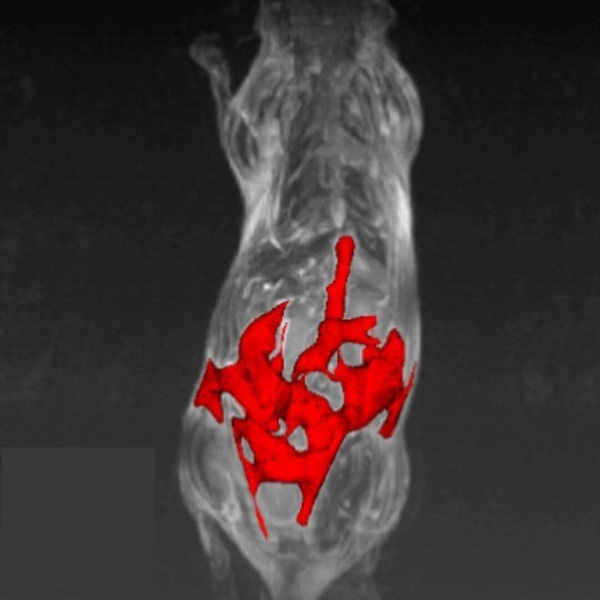

MRI is a complementary method to bioluminescence imaging in the detection of tumors allowing more precise assessment of the location and extent of orthotopic tumors (here an orthotopic model of prostate bone marrow metastasis).

MRI is a complementary method to bioluminescence imaging in the detection of tumors, allowing a more precise assessment of the location and extent of orthotopic tumors (here, an orthotopic model of prostate bone marrow metastasis). Image Credit: Scintica Instrumentation Inc